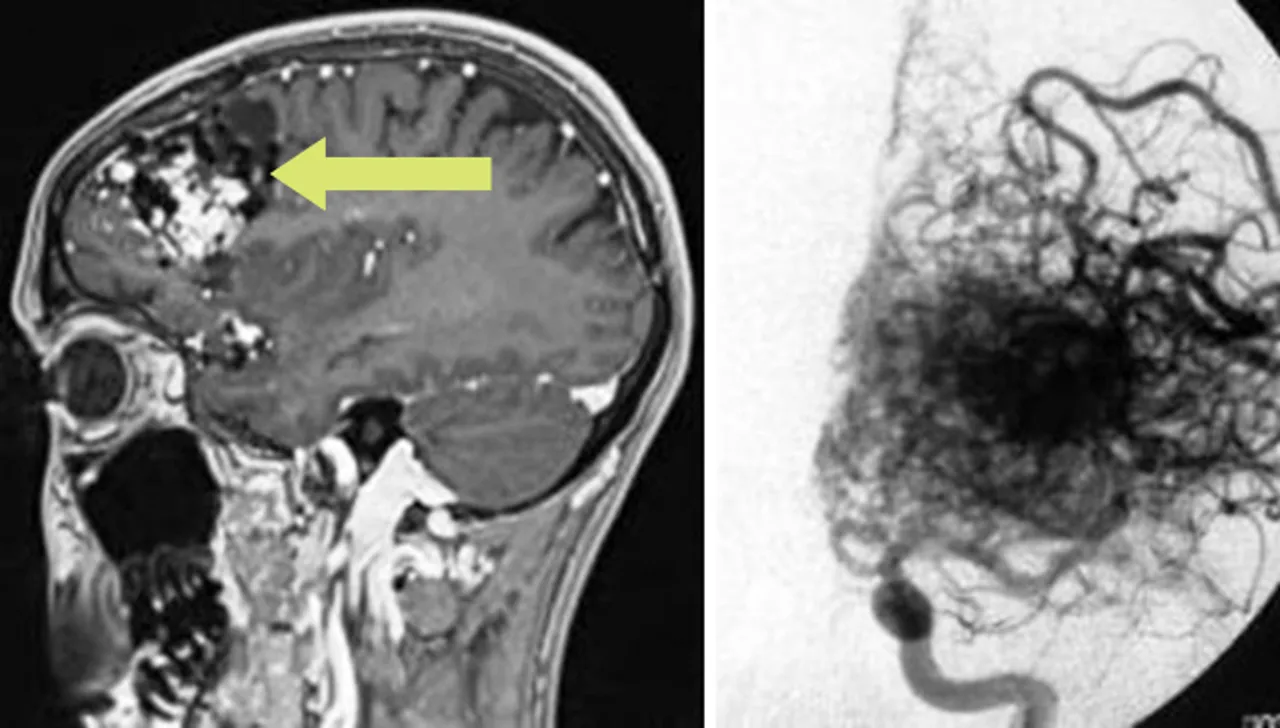

Магнитно-резонансная томография (МРТ) используется для точной локализационной диагностики патологического сосудистого клубка – здесь основное внимание уделяется взаимосвязи с функционально особо значимыми областями мозга. Поэтому МРТ является основным требованием для точного планирования лечения [1].

Левый: МРТ-изображение лобной артериовенозной мальформации.

Верно: Точное представление цифровой субтракционной

Цифровая субтракционная ангиография (ЦСА) также обеспечивает дополнительную визуализацию сосудистой архитектуры и динамики кровотока.